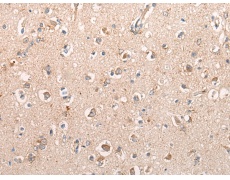

IHC positive control: |

Human brain |

IHC Recommend dilution: |

10-50 |